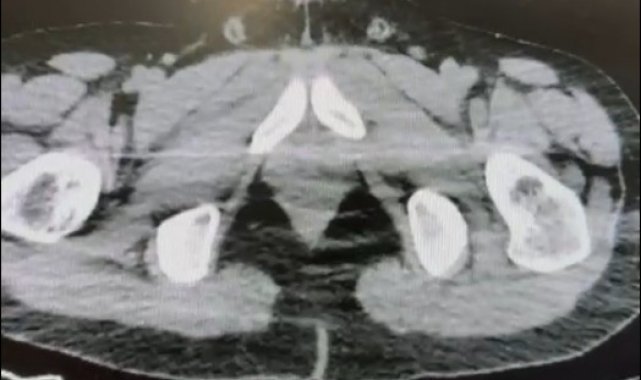

Nevşehir İl Emniyet Müdürlüğü Narkotik Suçlarla Mücadele Şube Müdürlüğü ekipleri, kentte uyuşturucu ve uyarıcı madde ticareti yapmak ve kullanmak suretiyle vatandaşları zehirleyen sokak satıcılarına yönelik çalışma başlattı. Cumhuriyet Başsavcılığı koordinesinde çalışmalarını yoğunlaştıran ekipler, şüpheliler S.B. ve O.R.'nin 'yutma yöntemi' ile kente uyuşturucu madde sevk edeceği bilgisi üzerine operasyon düzenledi. Şüphelilerin ikametlerinde ve araçlarında yapılan aramada 101 kapsül halinde 722 gram uyuşturucu madde, 1 adet hassas terazi, uyuşturucu madde sevkiyatında yutma yönteminde kullanılan muhtelif materyaller, uyuşturucu madde ticaretinden elde edilen 20 bin 210 TL, bin 320 euro ve 10 ABD doları ele geçirildi. Emniyetteki işlemlerinin ardından adliyeye sevk edilen 2 şüpheli, çıkarıldıkları mahkemece tutuklanarak cezaevine gönderildi.